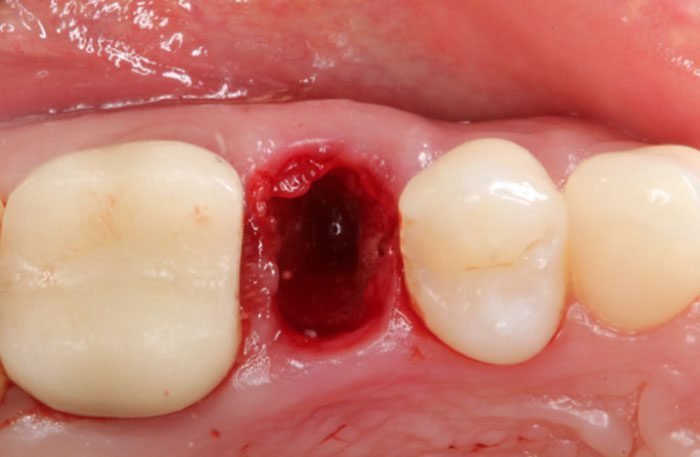

- CLINICAL VIDEO Socket Preservation after a Lower Molar Extraction using an

- Allograft and a d-PTFE Membrane | Dr Sascha A Jovanovic

- CLINICAL VIDEO Immediate Tooth Replacement of Failing Tooth #11 | Dr Sascha A Jovanovic

- CLINICAL VIDEO Immediate Implant Placement in the Esthetic Zone | Dr Robert Silva